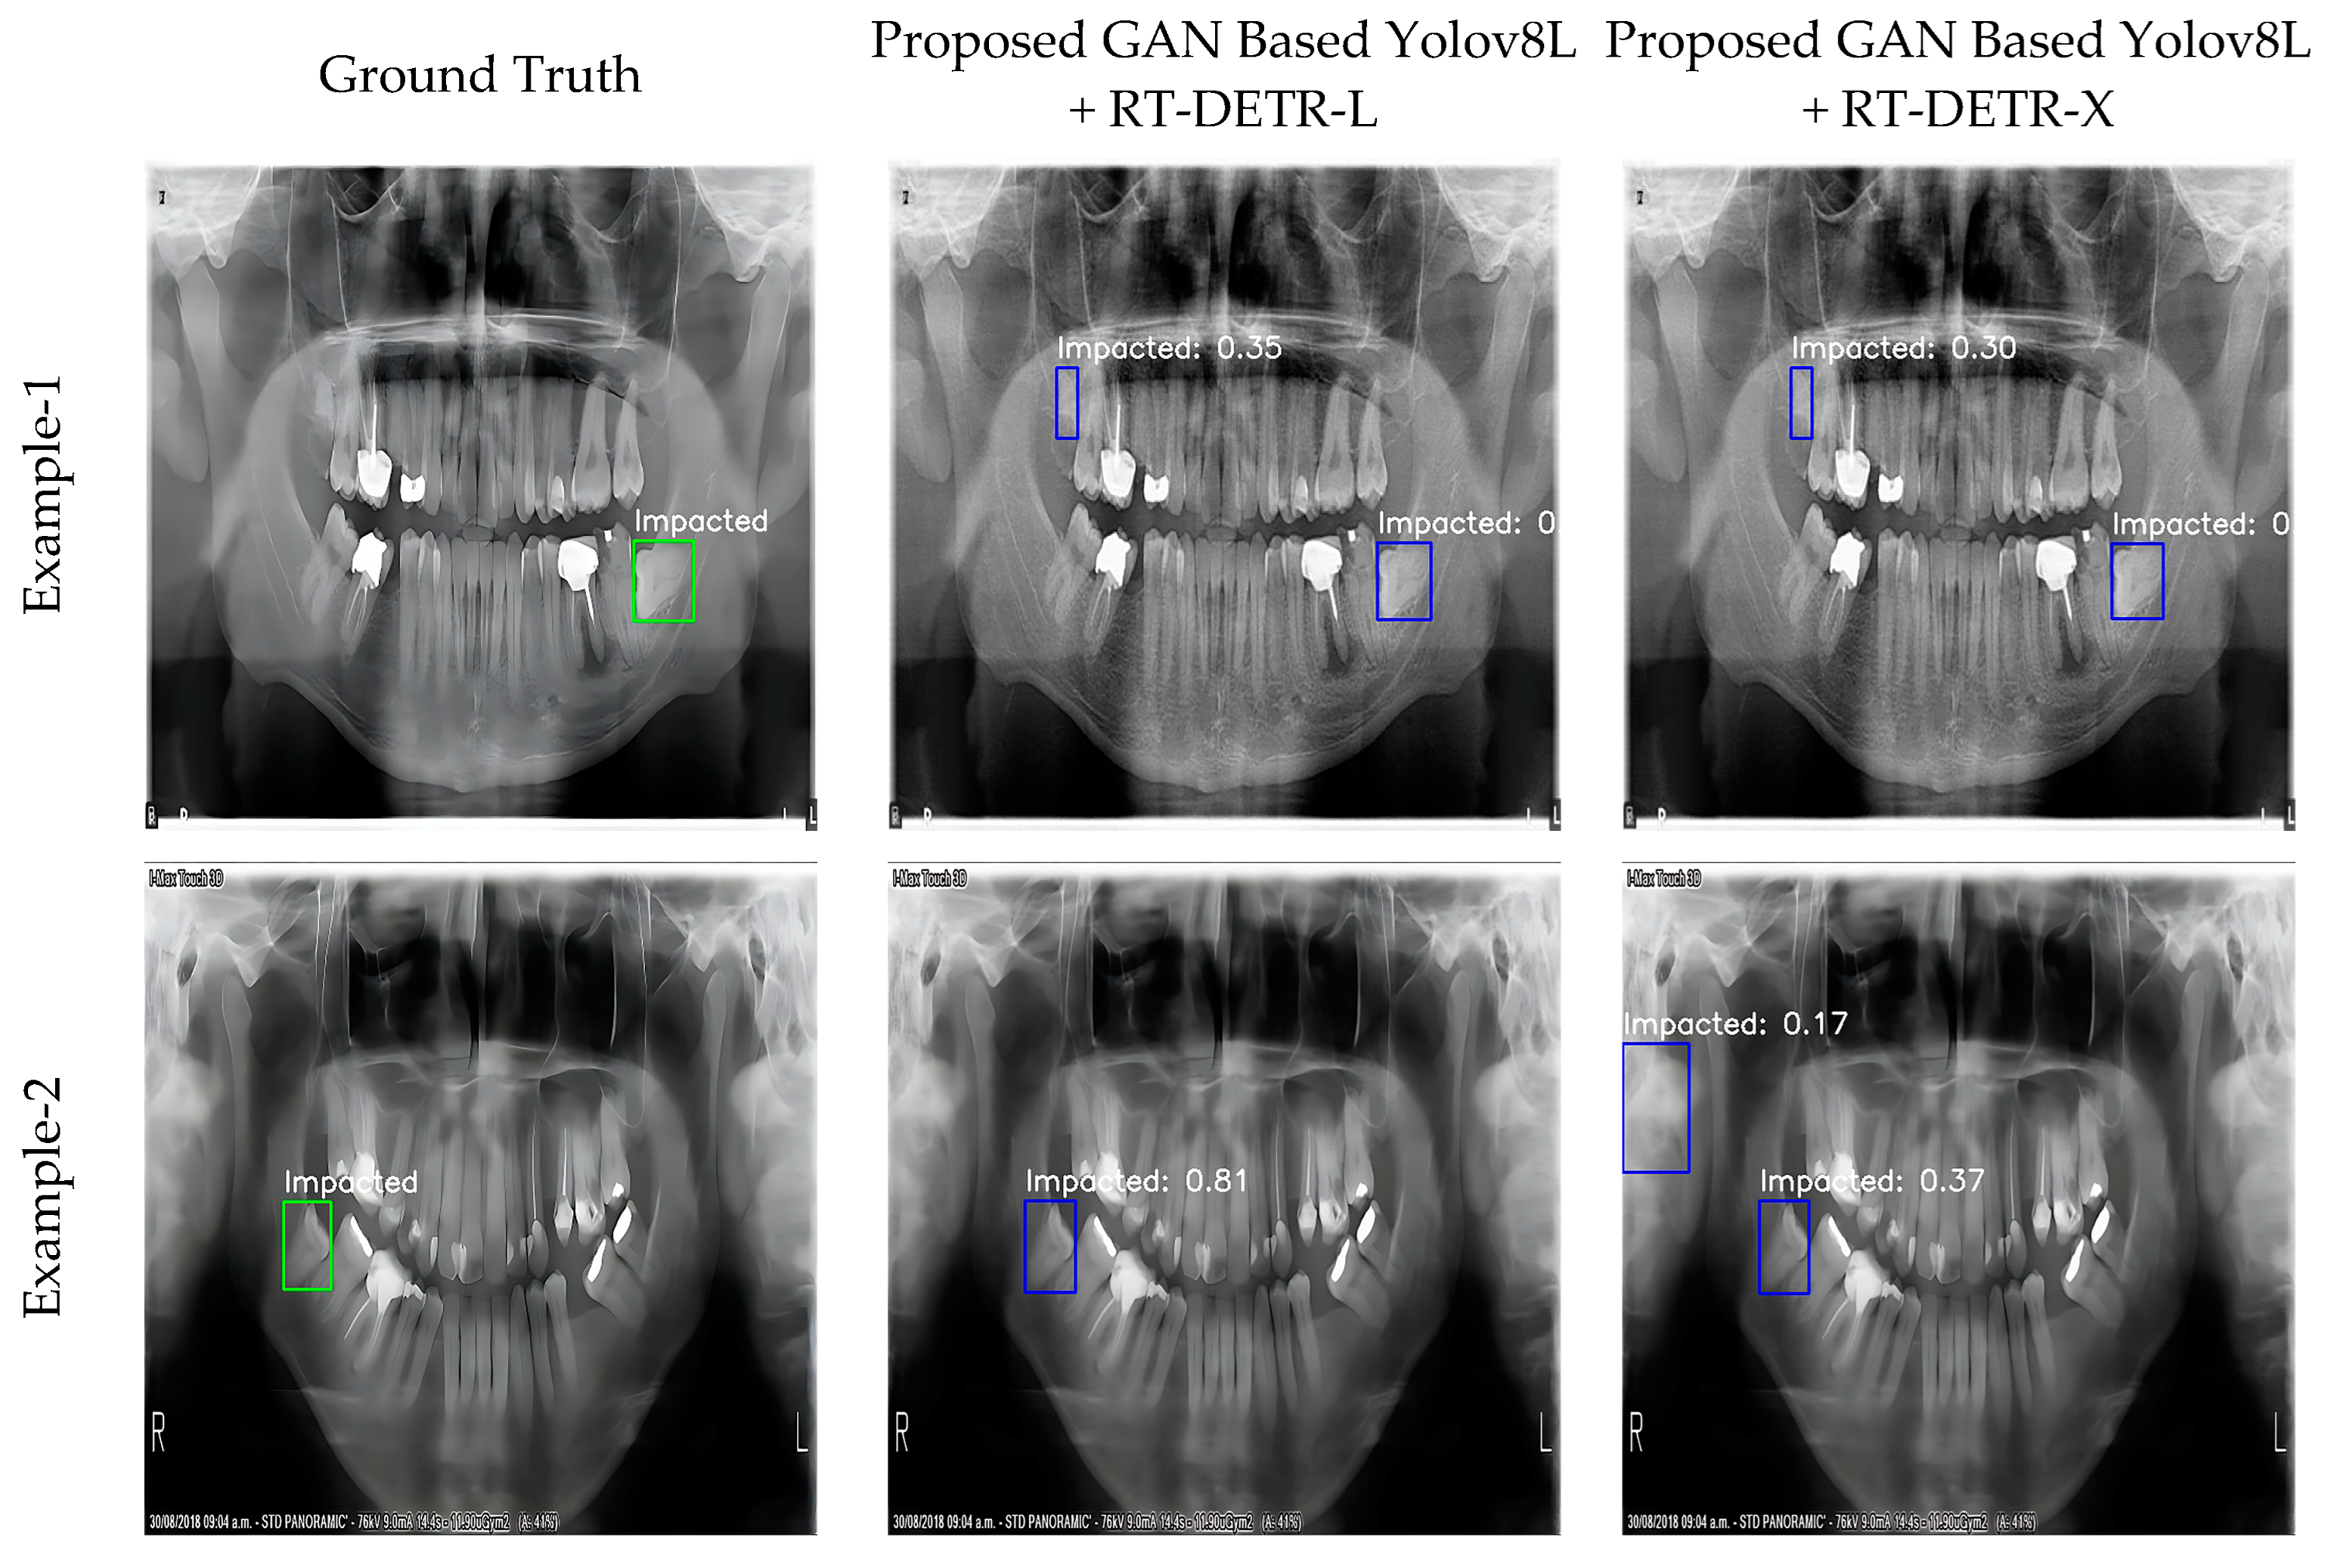

3.3. Optimized Results

- YOLOv8L + RT-DETR-L: This model showed the highest accuracy of 98.3% with mAP@0.5. This means that the overall recognition accuracy of the model is quite high. The recall rate reached a remarkable 99.2%, indicating that the model was able to correctly detect almost all target objects. However, the precision remained relatively low compared to the other metrics at 86.7%. This suggests that the model’s false positive prediction rate could be improved. The F1 score reached 92.5% in the balance of precision and recall. The optimized parameters of the WBF algorithm for this model were determined as follows:

- IoU Threshold (iou_thr): 0.3466;

- Skip Box Threshold (skip_box_thr): 0.0340;

- YOLOv8L Weight (weight1): 4.2111;

- RT-DETR-L Weight (weight2): 2.9897.

- YOLOv8L + RT-DETR-X: This model achieved a high accuracy of 97.5% mAP@0.5 and a remarkable performance with an F1 score of 96.0%. The precision was 93.8% and the recall 98.4%. This shows that the model provides a balanced and reliable performance. The optimized parameters of the WBF algorithm for this model were determined as follows:

- IoU Threshold (iou_thr): 0.3597;

- Skip Box Threshold (skip_box_thr): 0.0843;

- YOLOv8L Weight (weight1): 7.7882;

- RT-DETR-L Weight (weight2): 7.6551.

3.4. Visualization